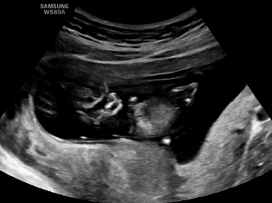

因为,NT检查时对宝宝有很严格的体位要求。

对,你没听错,就是要宝宝们(不是宝妈)躺平!躺平!躺平!不能侧躺、坐着、趴着,也不能低头,更不要伸懒腰……当然最好还不要乱动(超声医生们超爱的标准NT躺)。

标准NT躺

相信我,这绝对是宝宝一生中最早的一次全身“证件照”,比你拍上半身证件照严格多了。

NT,英文Nuchal Translucency,即颈项透明层(蓝色区域)。NT超声检查是孕早期一项重要的超声筛查项目,主要用于评估胎儿染色体染色体异常(如唐氏综合征)或其他严重结构畸形的风险程度。